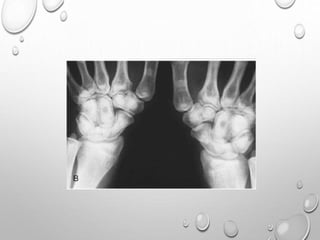

HANDS – LONG TUBULAR BONES ARE SHORT THICK , DELAY APPEARANCE OF IRREGULAR

EPYPHYSES

MARKEDLY SHORTENED ULNA , RADIUS AT WRIST , ESPECIALLY AT CENTER THEY ARE

HYOPLASTIC….GIVING V APPEARANCE